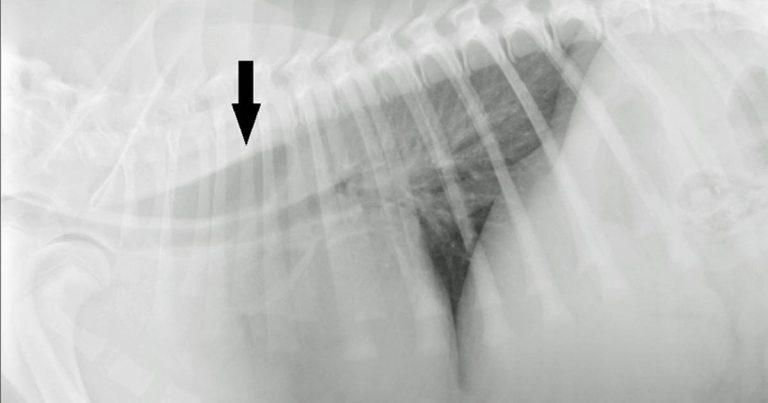

Radiographs of the thorax were performed (right lateral and dorsoventral; Figures 1 and 2, respectively).

From the dorsoventral view (Figure 2, black arrow), leftward tracheal deviation at the level of the cranial border of the heart was appreciated. No other mediastinal abnormalities were seen.

The lung fields showed normal opacity and volume, and no signs of aspiration pneumonia were present. The radiographic diagnosis was focal dilation of the oesophagus cranial to the heart base and left-sided deviation of the trachea.

These radiographic findings, together with the clinical history and patient’s age, were suggestive of vascular ring anomaly, causing constriction of the oesophagus and subsequent cranial dilation.

Given the leftward deviation of the trachea, persistent right aortic arch (PRAA) was very likely. Other possible, but much less likely, differential diagnoses were oesophageal stricture or an oesophageal foreign body.